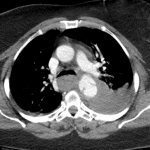

Age: 68

Sex: Female

Indication: Trauma

Sample ReportMild widening of the superior mediastinum with poor definition of the aortic arch, which raises concern for traumatic aortic injury. Recommend correlation with chest CTA.

Hazy opacification throughout the left hemithorax, which likely represents a combination of layering pleural fluid and airspace opacification related to atelectasis, contusion, and/or aspiration.